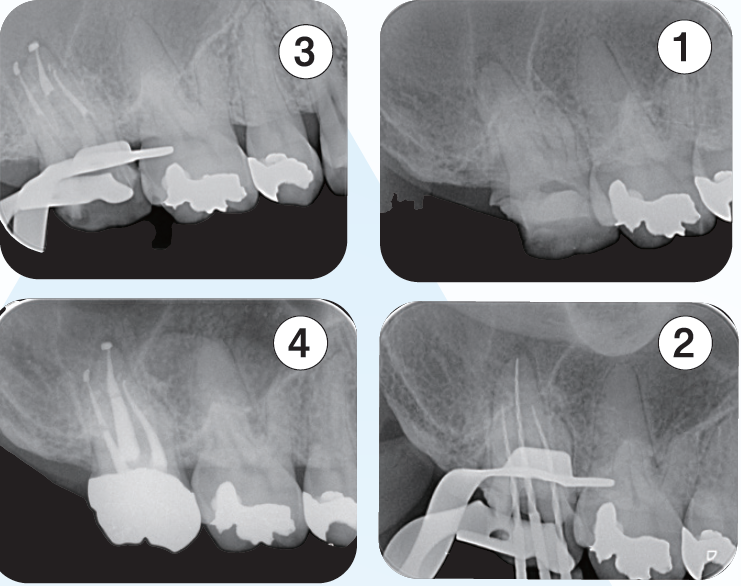

「臨床症例1」下顎左側第一大臼歯の咬合痛を主訴に来院

●年齢30代 男性

歯髄反応(―)であったため歯髄壊疽と診断し根管処置を行なった。根管口付近にある器具操作するには規制になるような形態に対して修正形成を行い、ファイルの根尖への到達性を確保して、根尖付近の根管拡大・形成を的確に行うため適正と思われるテーパーを付与し根管充填を行なった。根管充填材は根尖周囲組織にも炎症が疑われる透過像が認められていたため、より根尖周囲組織の殺菌・抗菌効果を得るために歯科材料として生体に為害作用が少ないと承認された歯科材料承認ClassⅢのシーラーを使用した。適正に根尖部にテーパーが付与できたため根尖周囲部の開口部に根管充填材が行き渡り、根尖部の封鎖が良好な結果が得られた。

<術前>

覆髄材が近心髄角部付近まで充填されていて慢性の刺激により歯髄腔の狭窄が見られる。近心根根管口付近は遠心方向への規制があり、器具の根尖部への到達性を妨げている。

<術後>

近心根の根管口付近は湾曲度の修正形成が行われ、比較的緩やかな湾曲根管の処置になった。遠心根は根管口から根尖部まで連続したテーパーが付与され、根管充填時のプラガーの圧は適正に伝わり、根尖付近の複数の開口部に根管充填材が行き渡っていることが確認できる。

「臨床症例2」複雑な湾曲を有する根管に対して対処したケース

●年齢50代 男性

咬合による歯冠破折から歯髄炎になり、根管処置が必要となる。器具操作が困難なため、紹介を受け当院を受診。近心頬側根管は根管口付近は狭窄を呈し、遠心方向に向けて開口しており、近心頬側根管の器具の挿入はかなり遠心方向から器具を回し込む必要があった。また根尖の開口部は近心方向にあり、根管の全体的な形態はS字のような形態を有する。全体的に湾曲度を緩やかになるよう処置を進めた。器具の選択に関しては、より柔軟性のあるマルテンサイトのニッケルチタンファイルを選択した。根管口付近の形態修正は器具が歯軸に対して極力平行になるように行なった。EMR時のレントゲン像では、3根管それぞれが歯軸に対してほぼ平行に挿入されていることが確認できる。しかしながら根尖部付近がそれぞれ大小の湾曲を有し、特に近心頬側根は近心方向に湾曲している。根管上部の形態修正とマルテンサイトのファイルの使用によって根尖への器具の到達に成功した。根管充填はウォームドガッタパーチャとMTAシーラーを用いセクショナル法で行った。術後4年弱のレントゲン像で、根尖周囲の歯周組織は安定していることが確認できる。

① 初診時(2021/06/21)

口蓋根根尖部には炎症による歯根膜腔の拡大が見られる

②EMR測定時

根管口付近の修正形成を行い、ファイルが歯軸に対して平行に入ることによって根尖部の湾曲に対してニッケルチタンファイルがその特性を活かし、元々の根管形態を崩さず追従し根尖部への到達を獲得できている

③根管充填時

それぞれの根の根尖部に根管充填材が到達していることが確認できる

近心頬側根根管は根尖部は近心方向に湾曲して開口しているのが確認できる

④補綴装置装着時

根管処置後臨床症状もなくレントゲン所見も安定している

⑤術後4年弱(2025/05/28)

臨床症状もなく経過良好であり、初診時に見られた口蓋根根尖部の歯根膜腔の拡大も改善し安定している